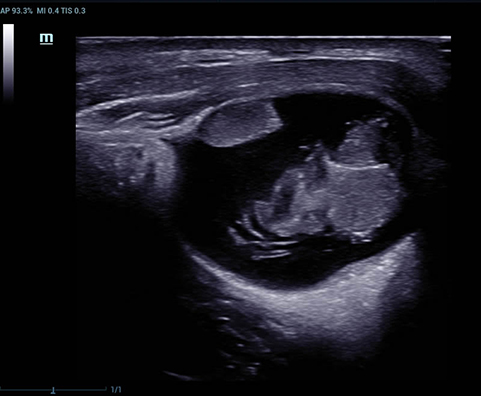

Desde su creaciÃģn, Mindray no ha dejado de explorar nuevas maneras de mejorar la fiabilidad del diagnÃģstico. Gracias a ZONE Sonography?, la tecnologÃa mÃĄs revolucionaria, la nueva plataforma ZST+ del Resona 7 eleva la calidad de imagen de ultrasonido mediante la adquisiciÃģn de zonas y el procesamiento de datos de canal.

AdemÃĄs de una calidad superior de la imagen, el Resona 7 tambiÃĐn mejora las capacidades de investigaciÃģn clÃnica gracias al revolucionario V Flow para la evaluaciÃģn hemodinÃĄmica vascular y la adquisiciÃģn de planos mÃĄs inteligente a partir de un conjunto de datos 3D para el diagnÃģstico CNS fetal. Combinando el funcionamiento multitÃĄctil mÃĄs intuitivo basado en gestos y todas las funciones clÃnicas esenciales, el Resona 7 estÃĄ realmente encabezando nuevas ondas en la innovaciÃģn del campo del ultrasonido.